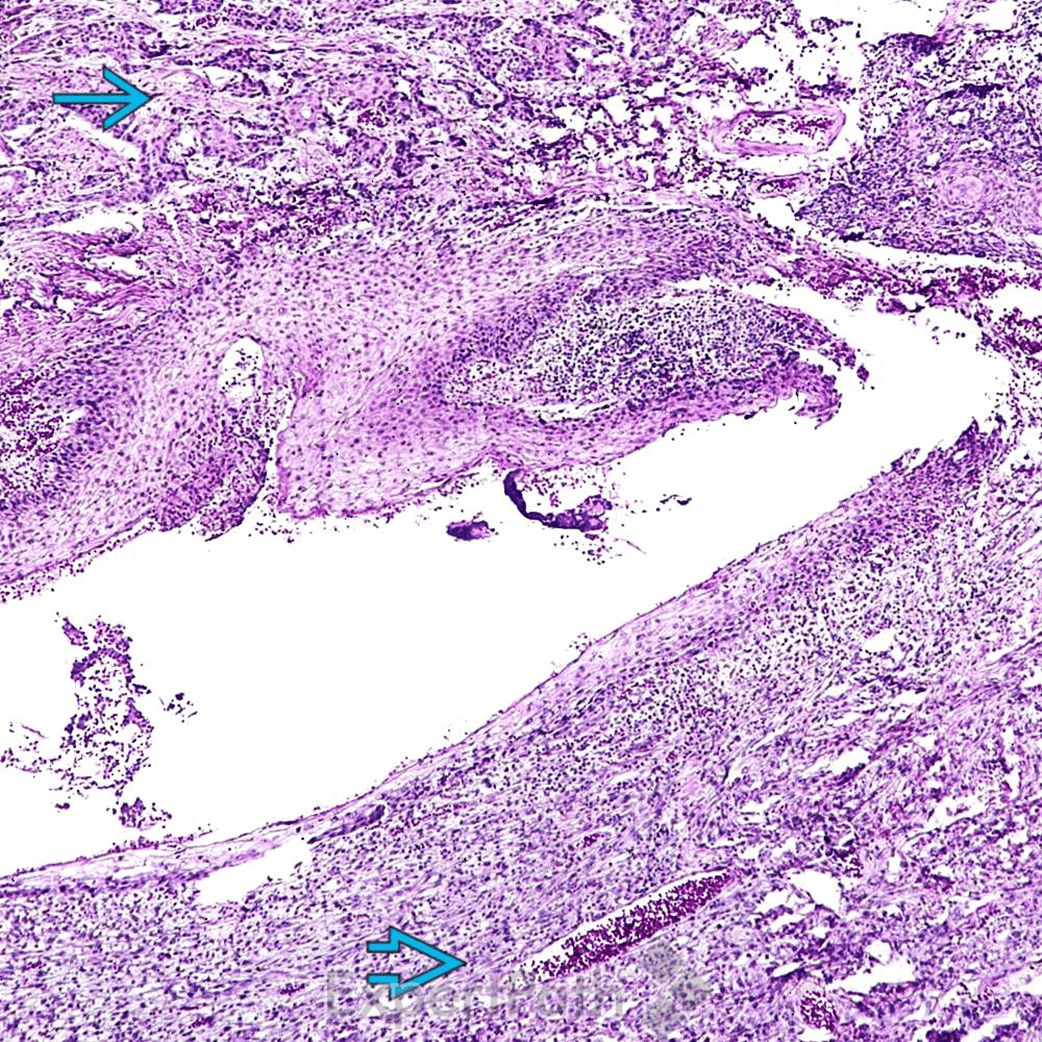

鱗狀上皮癌(Squamous Cell Carcinoma, SCC)

pictures from ExpertPath

basaloid SCC